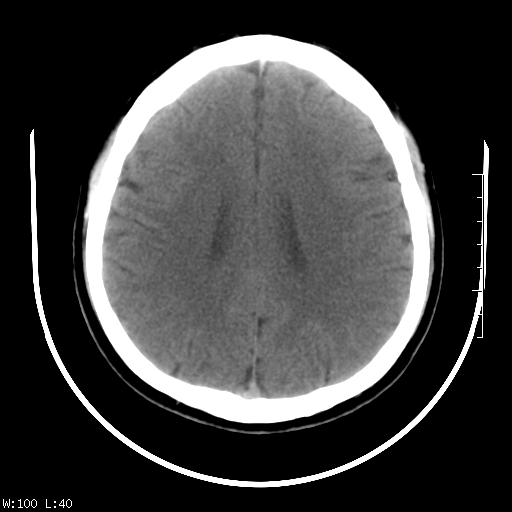

标题: CT22236:男,45,经常头痛。看看脑干正常吗? [打印本页]

标题: CT22236:男,45,经常头痛。看看脑干正常吗?

未见明显异常,建议ct增强或mri检查。

没见异常密度及形态改变啊,我认为是正常的。

颅脑ct轴位平扫颅内未见明确异常。

颅脑ct平扫未见明确异常,必要时mri检查。

颅脑ct平扫未见异常